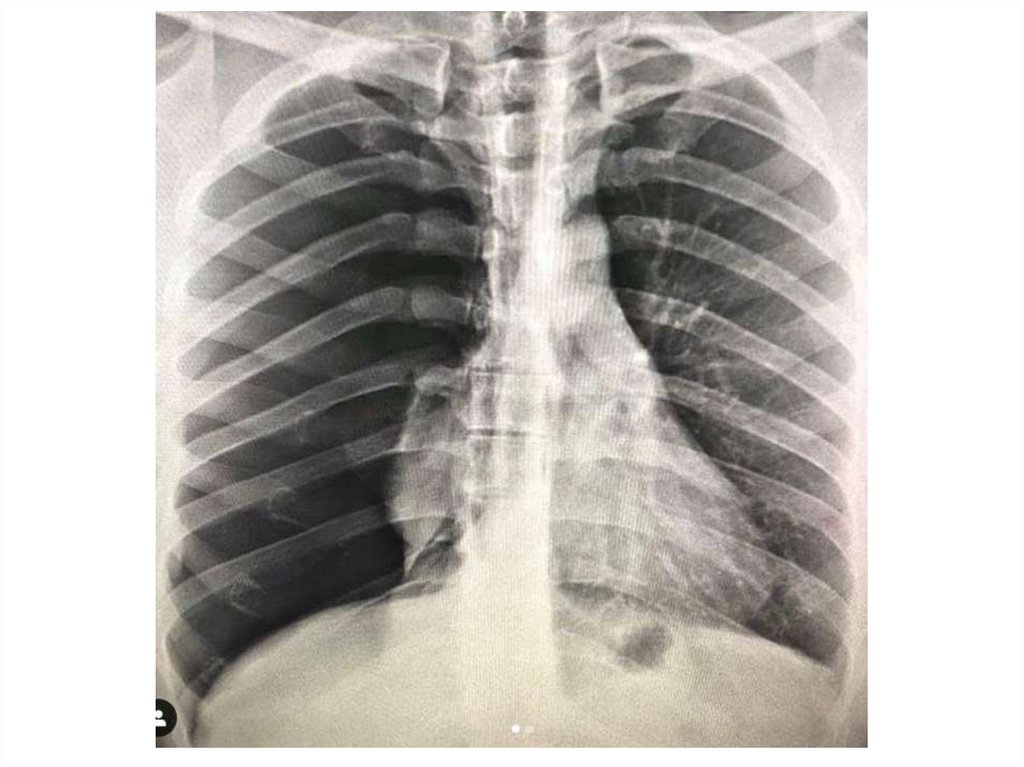

Назовите

• Вид исследования

• Область исследования

• Патологию